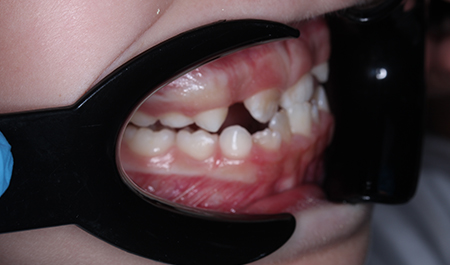

Коррекция мезиального прикуса у ребенка

ЖалобыМама пациента заметила формирование неправильного прикуса и изменение лицевых параметров (признаки мезиального прикуса).

Достигнуто правильное резцовое перекрытие, что позволило устранить обратную резцовую окклюзию и значительно снизить риск оперативного вмешательства в будущем. Следует учитывать, что генетические факторы и дальнейший рост нижней челюсти могут влиять на результат, однако на данный момент риск хирургической коррекции существенно уменьшен.

До